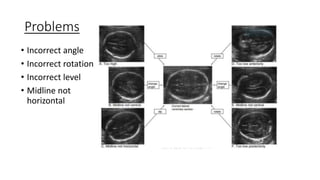

Problems

• Incorrect angle

• Incorrect rotation

• Incorrect level

• Midline not

horizontal

Problems • Incorrect angle •Incorrect rotation • Incorrect level • Midline not horizontal